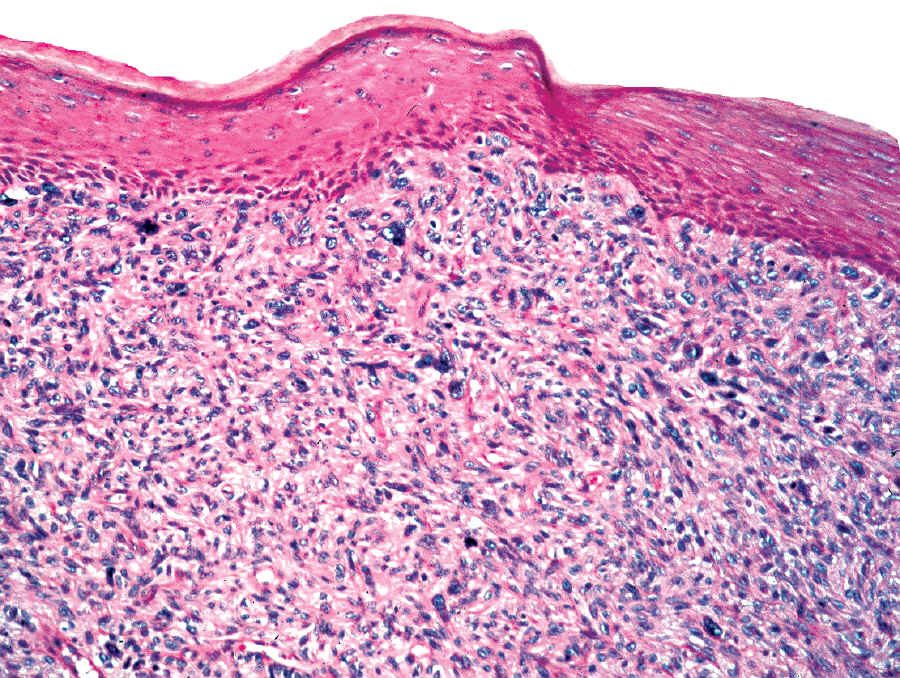

Case #3

81 year old man with a 2 cm red nodule in the skin of the face.